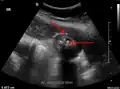

Right upper quadrant abdominal ultrasound is most commonly used to diagnose cholecystitis.[1][26][27] Ultrasound findings suggestive of acute cholecystitis include gallstones, pericholecystic fluid (fluid surrounding the gallbladder), gallbladder wall thickening (wall thickness over 3 mm),[28] dilation of the bile duct, and sonographic Murphy's sign.[13] Given its higher sensitivity, hepatic iminodiacetic acid (HIDA) scan can be used if ultrasound is not diagnostic.[13][14] CT scan may also be used if complications such as perforation or gangrene are suspected.[14]

Abdominal ultrasonography showing gallstones, wall thickening and fluid around the gall bladder

Acute cholecystitis as seen on ultrasound. The closed arrow points to gallbladder wall thickening. Open arrow points to stones in the GB